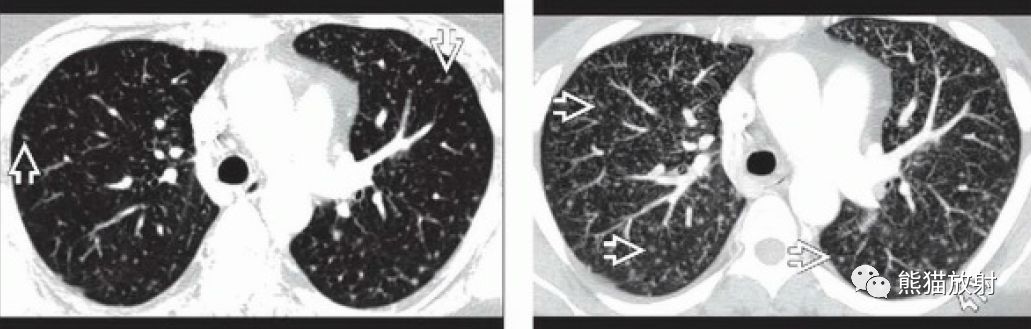

(右 慢性淋巴细胞白血病患者,双肺弥漫性粟粒性肺结节,继发于mac感染

粟粒型肺结节,随机分布.